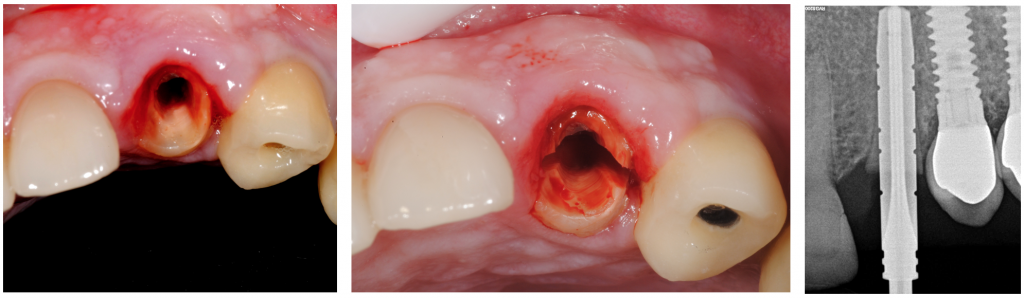

La extracción conservadora del fragmento de la raíz palatina se realizó con unas pinzas especiales, y el alvéolo se desbridó suavemente y se irrigó con solución salina normal.

Se realizó la preparación del lecho del implante en la pared palatina del alvéolo y se colocó un implante en forma de raíz (Klockner ®KL (4,2x12 mm)) según las recomendaciones del fabricante sin contacto con el escudo.

La posición apicocoronal de la plataforma del implante era 1 mm apical a la encía marginal palatina. Se dejó el espacio entre el escudo y la superficie del implante para permitir la formación de coágulos de sangre.

El torque final fue de 50nm, y se optó por hacer carga inmediata no funcional mediante la ferulización del provisional al implante de los dientes 24.